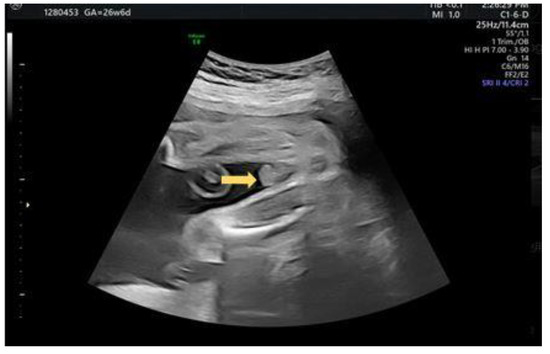

2.1. Case 1